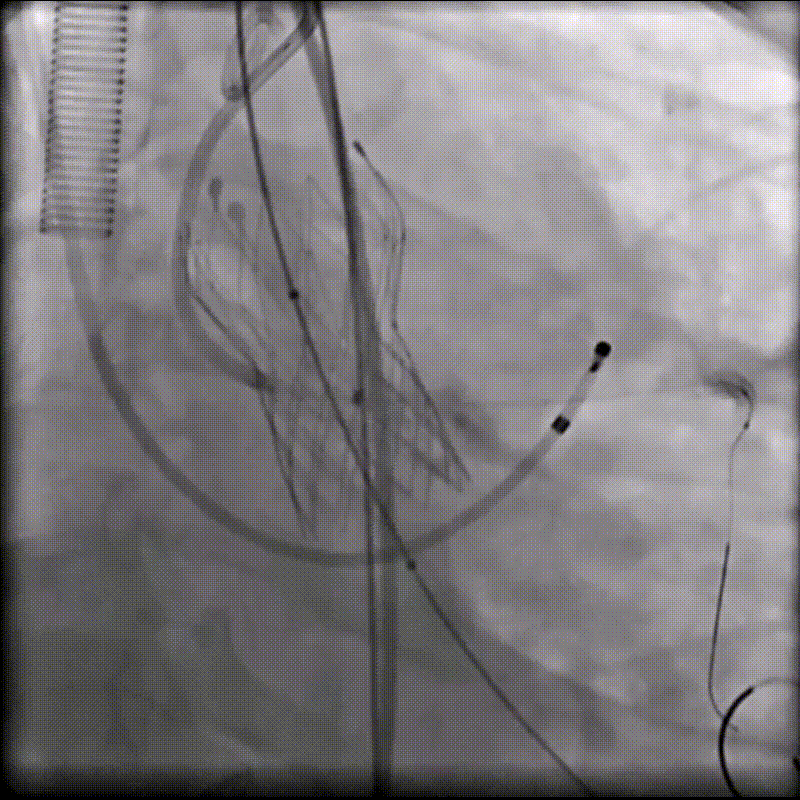

(1)Type 0二叶式主动脉瓣,瓣环适中,中度钙化,Type 0二叶瓣受瓣口形态及钙化影响,瓣架呈非理想椭圆形展开,对瓣架支撑力与顺应性提出了更高要求,同时该病例合并升主扩张,对同轴性和释放的稳定性提出了更高的要求。因此优先选择支撑性和顺应性兼具的瓣膜,以及较柔软花冠的瓣膜,降低对升主动脉的损伤,小锥角的设计进一步提升了瓣膜在释放的稳定性

(2)窦部空间较小,左侧瓣叶冗长,且开口位置在短轴平面,左冠冠脉风险较高,优先选择有收腰设计的瓣膜,降低冠脉风险并保留术后足够的VTC

综合病例解剖特点及患者年纪,决定使用第二代可回收的自膨瓣,可回收提高容错空间,为了降低冠脉阻挡风险,决定采用平衡收腰设计的TaurusElite 的瓣膜,先使用大鞘鞘芯进行预扩,然后上20F大鞘。

麻醉医师:患者本次因间断胸闷3年,再发伴加重2月就诊于我院,拟行经导管主动脉瓣置换术,麻醉选择气管插管全身麻醉,备体外循环,术中密切监测生命体征,维持血流动力学,考虑到冠脉风险,球囊预扩和瓣膜释放之后,严格监测血压和心率的变化。

超声医师:患者为重度主动脉瓣狭窄,术前超声充分评估,心腔大小,心腔容量是否充分,各瓣叶活动程度,该病例左侧冠脉风险较高,工作位以及最终释放超声下充分评估原生瓣叶到左冠侧瓣叶距离,进一步评估冠脉风险。